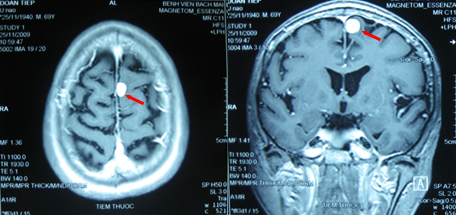

4 dấu hiệu sớm của khối u não, người mắc nên đi khám ngay